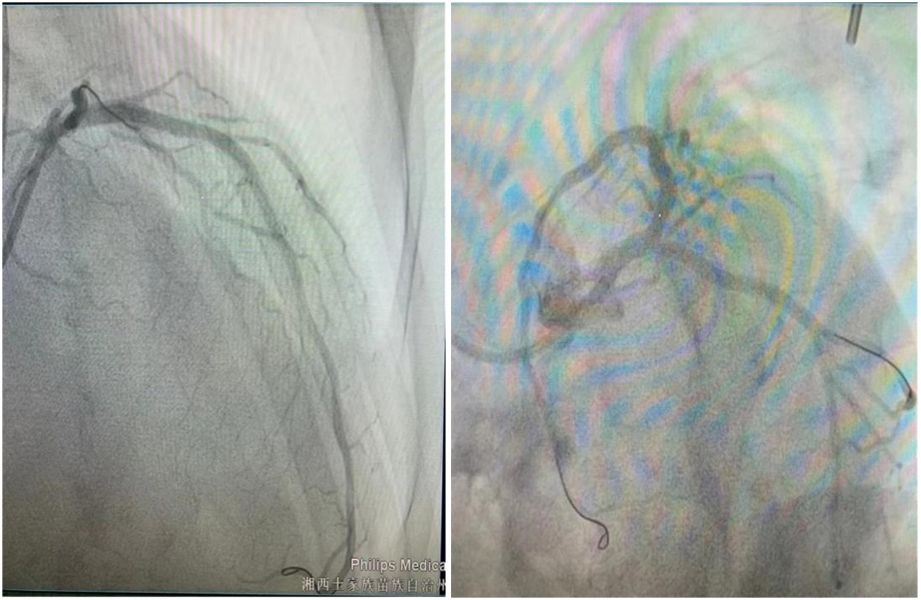

术后造影 钙化病变是冠脉介入治疗的“拦路虎”,在术中会使得球囊、支架等器械难以通过病变位置,不仅支架脱载风险高,还可能导致支架贴壁不良、膨胀不全,甚至在支架内形成血栓造成急性冠脉闭塞,让手术难度和风险成倍增加,而且远期支架内再狭窄率也会显著地增加。

在血管内超声技术指引下,该科介入团队采用高速旋磨头“分次旋磨”的方法,成功为宋大爷清除了冠脉内钙化斑块最严重的部分,使狭窄的管腔变大,内膜变光滑,扫除了手术最大的障碍。随后经过冠脉球囊扩张,顺利植入支架,使宋大爷的左主干至前降支恢复正常血流。最后,通过血管内超声检查,显示支架膨胀贴壁良好,管腔面积恢复满意,手术顺利完成。

术后造影